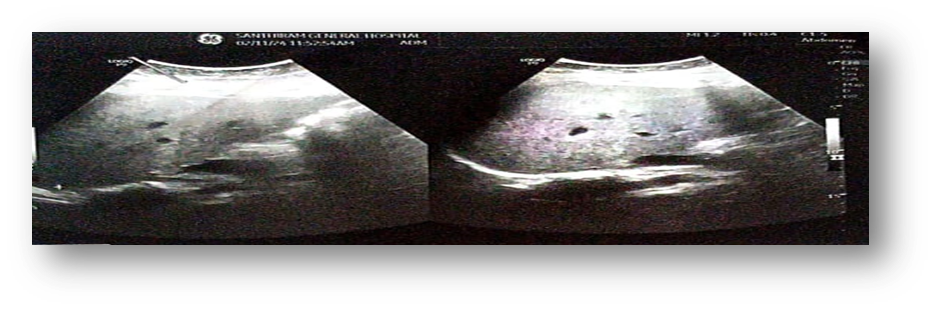

After the patient was stabilized in the ER she was shifted to General medicine department and appropriate treatment was given. On second day of hospitalization patient was advised for thyroid profile and results were within normal range. The reticulocyte count is increased(1.9%) indicating chances of hemolytic anaemia that need to be ruled out once the patient is recovered from the ADR. The 24 hours urine proteins were found to be exceeding the normal range (297mg/day). The Ultrasound scan of abdomen had shown increased echogenicity of liver along with hepatomegaly giving the impression of Grade-II fatty liver.

Figure2. USG scan of abdomen showing Grade-II fatty liver